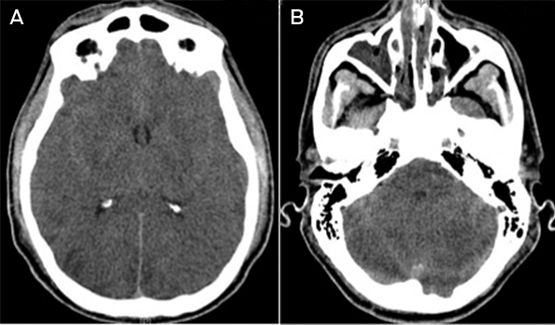

About 24 hours after the cardiac arrest, the patient developed signs of raised intracranial pressure with fixed dilated pupils and haemodynamic instability; he did not respond to noxious stimuli and he had lost brain stem reflexes. A non-contrast computed tomography scan of his brain showed diffuse cerebral oedema with tonsillar herniation and multiple areas of cerebral infarction (Box 2). About 43 hours after the cardiac arrest, the patient was declared brain dead by clinical criteria, and supportive care was withdrawn.